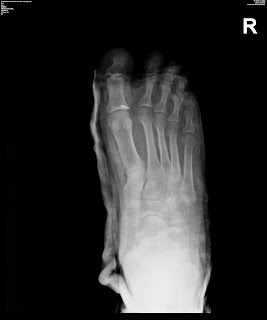

The second through fifth toes have a proximal, middle and distal phalanx. This material may not otherwise be downloaded, copied, printed, stored, transmitted or reproduced in any medium, whether now known or later invented, except as authorized in writing by the AAFP. The great toe has only a proximal and distal phalanx. Diagnosis can be confirmed with orthogonal radiographs of the involve digit. Most broken toes can be treated without surgery. Referral is indicated in patients with circulatory compromise, open fractures, significant soft tissue injury, fracture-dislocations, displaced intra-articular fractures, or fractures of the first toe that are unstable or involve more than 25 percent of the joint surface.

The first and fifth toes are most commonly involved as these are the border digits. Copyright 2023 Lineage Medical, Inc. All rights reserved. Referral also is recommended for children with first-toe fractures involving the physis.4 These injuries may require internal fixation. Diagnosis is made with plain radiographs of the foot. Joint hyperextension and stress fractures are less common.

Fractures of the toe are one of the most common lower extremity fractures diagnosed by family physicians. The second through fifth toes have a proximal, middle and distal phalanx. Web5th Metatarsal Base Fractures are among the most common fractures of the foot and are predisposed to poor healing due to the limited blood supply to the specific areas of the 5th metatarsal base. CLINICAL ANATOMY. WebPhalangeal fractures are the most common fracture of the forefoot.

MTP joint dislocations. Diagnosis is made with plain radiographs of the foot. The second through fifth toes have a proximal, middle and distal phalanx. The first and fifth toes are most commonly involved as these are the border digits. Nondisplaced phalanx fractures are managed with splint immobilization. most common injuries to the skeletal system, distal phalanx > middle phalanx > proximal phalanx, 40-69 years old - machinery is most common, displacement of proximal phalanx fracture, proximal fragment flexed due to interossei, distal fragment extends due to central slip, dynamic stability from compressive forces during pinch and grip, passive stabiltiy from collateral ligament, terminal slip of EDC inserts on dorsal aspect of middle phalanx, dominant artery found on median side of phalanges (closer to midline), type III - unstable bicondylar or comminuted, due to inherent stability provided by an intact and prolonged FDS insertion, proximal fragment in extension (due to central slip), results from hyperextension injury or axial loading, unstable if > 40% articular surface involved, represents avulsion of collateral ligaments, usually stable due to nail plate dorsally and pulp volarly, often associated with laceration of nail matrix or pulp, shearing due to axial load, leading to fracture involving > 20% of articular surface, avulsion due tensile force of terminal tendon or FDP, leading to small avulsion fracture, terminal tendon attaches to proximal epiphyseal fragment, deformity (angular, rotation, shortening), proximal fragment pulled into flexion by interossei, distal fragment pulled into extension by central slip, apex volar angulation if distal to FDS insertion, apex dorsal angulation if proximal to FDS insertion, diagnosis confirmed by history, physical, and orthogonal radiographs, extraarticular fractures with < 10 angulation or < 2mm shortening and no rotational deformity, 3 weeks of immobilization followed by aggressive motion, extraarticular fractures with > 10 angulation or > 2mm shortening or rotational deformity, Unstable patterns include spiral, oblique, fracture with severe comminution, Eaton-Belsky pinning through metacarpal head, minifragment fixation with plate and/or lag screws, lag screws alone indicated in presence of long oblique fracture, nail matrix may be incarcerated in fracture and block reduction, distal phalanx fractures with nailbed injury, dorsal base fractures with > 25% articular involvement, displaced volar base fractures with large fragment and involvement of FDP, Apex volar angulation effectively shortens extensor tendon and limits extension of PIPJ, indicated when associated with functional impairment, corrective osteotomy at malunion site (preferred), metacarpal osteotomy (limited degree of correction), most atrophic and associated with bone loss or neurovascular compromise, Lunate Dislocation (Perilunate dissociation), Gymnast's Wrist (Distal Radial Physeal Stress Syndrome), Scaphoid Nonunion Advanced Collapse (SNAC), Carpal Instability Nondissociative (CIND), Constrictive Ring Syndrome (Streeter's Dysplasia), Thromboangiitis Obliterans (Buerger's disease).

Unless it is fairly subtle, rotational deformity should be corrected by further manipulation. Toe fractures, especially intra-articular fractures, can result in degenerative joint disease, and osteomyelitis is a potential complication of open fractures. Distal Phalanx Distal phalanx fractures are usually nondisplaced or comminuted fractures. The great toe has only a proximal and distal phalanx.

On exam, he is neurovascularly intact. A combination of anteroposterior and lateral views may be best to rule out displacement. The first phalanx (great toe) is most frequently involved.

In many cases, anteroposterior and oblique views are the most easily interpreted (Figure 1, top and bottom).